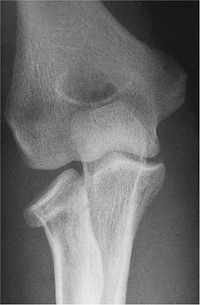

the elbow, disrupting the medial collateral ligament and causing a

compression fracture of the neck of the radius (Fig. 5-16).

The technique described earlier was employed to insert a miniplate at

the margin of the radial head after the fracture was reduced (Fig. 5-17). At 1 year the fracture has healed (Fig. 5-18)

and the patient has a range of motion of 10 to 145 degrees, flexion of

70 degrees, and supination of 80 degrees. There is no pain.

![]() |

|

Figure 5-16. A radial/head neck fracture dislocation in a 38-year-old physician.